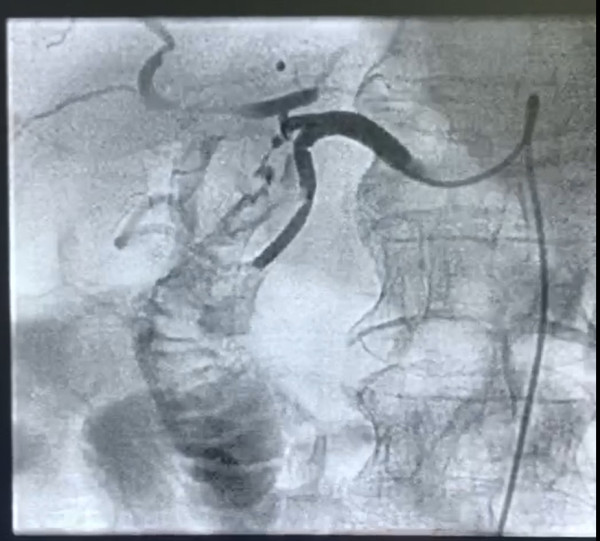

术中因患者失血过多、动脉搏动已几乎触摸不到,罗主任靠长期以来积累的手术经验迅速穿刺成功,并在最短的时间内完成血管造影并准确地找到出血责任血管。可见腹腔动脉一支分支血管有明细造影剂外溢,并可见肠道显影,遂超选择到责任血管并给予栓塞弹簧圈、明胶海绵颗粒、栓塞微球给予栓塞。

图2:术中栓塞责任血管,出血停止